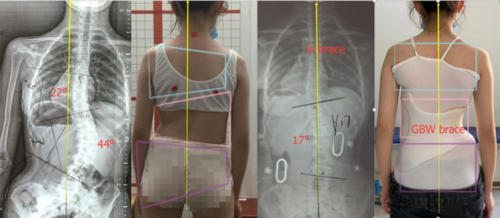

يعتمد العلاج على درجة زاوية كوب وعمر المريض:

العلاج الطبيعي: لتحسين استقامه الظهر وتقوية عضلات الظهر.

الأحزمة الطبية (الدعامات):لتعديل الانحناء خاصة في المراهقين أثناء النمو.

الجراحة: للحالات الشديدة (زاوية كوب ≥ 50 درجة) لتصحيح الانحناء واستقرار العمود الفقري.

زاوية كوب أداة أساسية في تشخيص ومتابعة اعوجاج العمود الفقري، إذ تساعد على تحديد شدة الانحناء وخطة العلاج المناسبة. ورغم وجود بدائل حديثة أكثر دقة، تبقى زاوية كوب المعيار الطبي المعتمد عالميًا.

الاعوجاج حالة مستمرة قد تحتاج تدخلًا في مراحل مختلفة من العمر. وبفضل وجود تقنيات التصنيف المعتمدة ، يمكن للأطباء تصميم خطة علاجية مخصصة تضمن تدخلاً جراحيًا عند الضرورة أو العلاج غير الجراحي قبل ذلك، لتفادي الاضطراب في الوظائف التنفسية أو أي أعراض متأخرة. فريقنا المحترف يضم نخبة من الأطباء والمتخصصين الذين يجمعون بين الخبرة والاحترافية لتقديم خطة علاجية شاملة ومخصصة لحالتك، تضمن السيطرة على الانحناء ومنع زيادته.